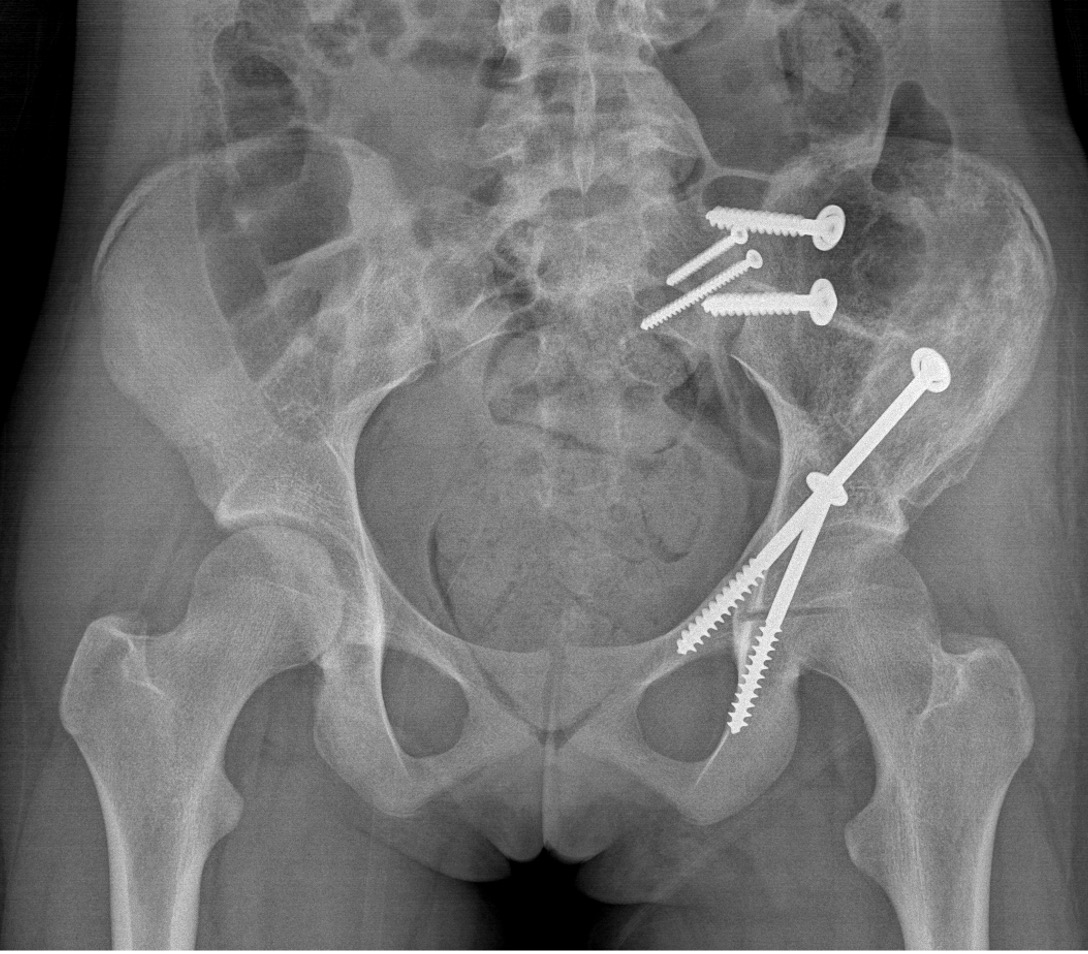

Wide Resection - limb salvage / amputation

2 cm margin of normal tissue if able

Assess histological response